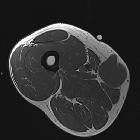

MRI

The tumor frequently demonstrates cystic foci. Signal characteristics include

- T1: isointense to muscle

- T2 non-fat suppressed: intermediate to hypointense to neighboring fat

- T2 FS: predominantly hyperintense